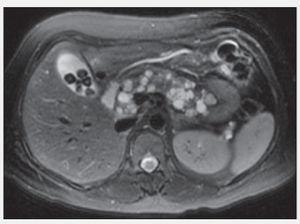

Estudios de imagen:Figura 1. Quistes pancreáticos.

Figura 2. Quistes pancreáticos y renales.